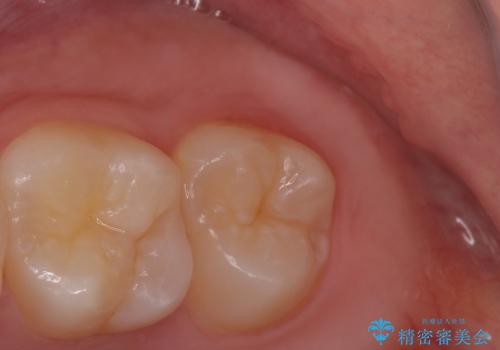

- 親知らずの抜歯希望で来院されました。

左側の親知らずを上下同時に抜いていきます。

時間は約60分で施術しました。